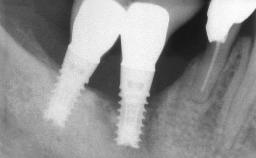

A 30-year-old female patient was referred to the Department of Periodontology of the University of Bern, Switzerland, by a dentist in private practice. Tooth 45 had been congenitally missing and had been replaced with a titanium implant three years prior to the first visit at the Department of Periodontology. The tissue level implant had a diameter of 4.1 mm, a length of 12 mm, and a sandblasted and acid-etched (SLA) surface (Straumann® Dental Implant System; Institut Straumann AG, Basel, Switzerland). The metal-ceramic crown on implant 45 had been cemented permanently. Implant 45 had been diagnosed with peri-implantitis by the referring dentist in the course of regular supportive care.